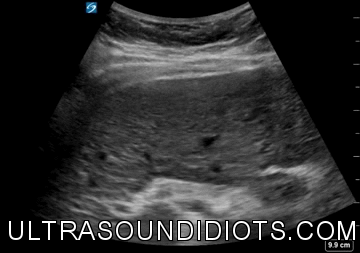

Gallbladder Lecture - Jones

Biliary

Limited Abdomen - Cholecystitis

pancreatic pseudocyst

Hydronephrosis